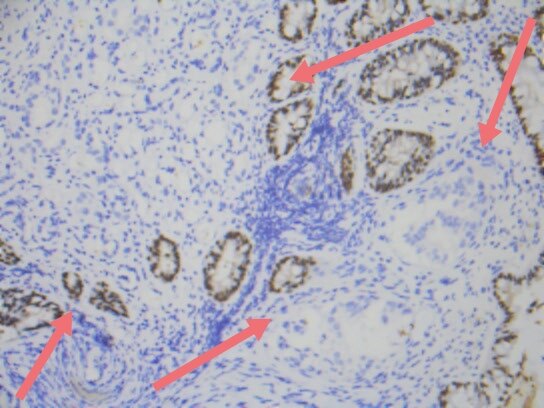

上述免疫组化结果辅助诊断为前列腺腺泡腺癌累及直肠。

加上上述实验室检查,血清psa升高显著,前列腺腺泡腺癌累及直肠就确诊了。所以,老年男性,直肠占位,不能忽视前列腺癌累犯。上述案例,也一再显示癌的发生发展,很长时间内都是静悄悄的,癌可以逃逸人体免疫系统的监控,而疯狂的无序无节制生长,直到破坏了关键器官或组织,才会引起相应的症状。为此,中老年人,规范的健康体检,规范的肿瘤筛查和血清肿瘤标记物的检测,都是十分必要的。当然,我们自己对自己健康的关注才更加重要。了解自己的身体,关注自己的健康,增加健康常识和健康意识都是重要和必需的。